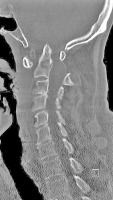

Abbildung 3: Seitliche Röntgenverlaufskontrolle einer subaxialen Subluxation nach 2-jährigem Verlauf. Zunehmendes Treppenstufenphänomen der Segmente HW 3/4 und 4/5. Zustand nach transartikulärer Verschraubung von HWK 1/2 4 Jahre zuvor.

Keywords: Röntgensubaxialen Subluxationtransartikulärer VerschraubungTreppenstufenphänomenVerlaufskontrolle